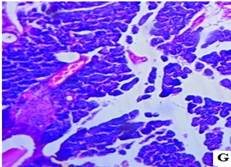

The histopathological studies of the pancreatic tissues are shown in (fig. 3). Normal rats showed the normal architecture of the pancreas with the preserved islet of Langerhans cells (fig. 3A). Induction of diabetes using Streptozotocin resulted in hyalinization of islets of Langerhans cells with focal mild degenerative changes, mild fibrosis, dilated and congested vessels along with focal chronic inflammatory cell infiltrate in diabetic rats (fig. 3B). HFT control rats showed mild edema of islets of Langerhans cells, thick-walled and congested vessels, focal lymphocytic infiltrate exhibiting focal edematous changes (fig. 3C). The abnormal histopathology of the pancreas due to Streptozotocin-induced diabetes was reversed in the Glibenclamide, and EAFBN treated diabetic animals.

The recovery of standard Glibenclamide treated group was evident as near normal architecture with preserved islet cells and mild edema (fig. 3D). The resulted in EAFBN (100 mg/kg, 200 mg/kg & 400 mg/kg) treated groups mild hyalinization islets of langerhans cells with focal mild degenerative changes when compared to untreated diabetic rats. It can be noted that the islets of langerhans cells regenerated in the treatment groups (fig. 3E,3F& 3G).

Fig. 3: Histology of control and treated rat pancreas of antidiabetic studies. A) Control rat, B) Diabetic control, C) HFT control, D) Standard, E) EAFBN (100 mg/kg), F) EAFBN (200 mg/kg) and G) EAFBN (400 mg/kg)